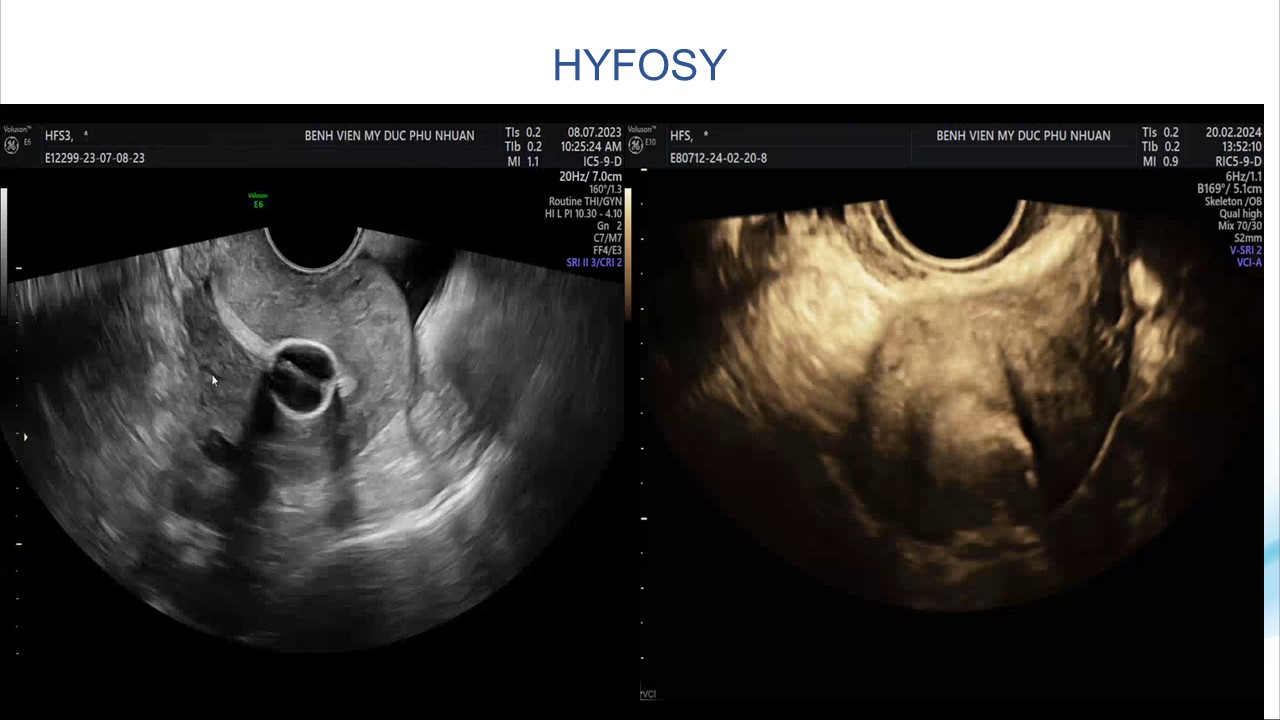

Siêu âm sử dụng chật tương phản trong phụ khoa

BS. CKI Phạm Thị Phương Anh - Bệnh viện Mỹ Đức